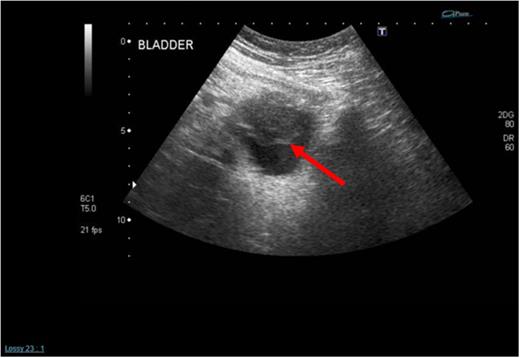

An urgent transurethral resection of the bladder tumour (TURBT) was performed which demonstrated a solid 4 cm tumour in the anterior wall of the urinary bladder. Resection was complete and tissue sent for histopathological analysis. A staging computed tomography (CT) scan post-op confirmed the absence of any locally advanced disease, lymphadenopathy or distant metastases (Fig. 2). Initial histopathological analysis reported the presence of muscle-invasive Grade 3 transitional cell carcinoma of the bladder with sarcomatoid change (G3pT2), but a supplementary report soon after confirmed positive smooth muscle actin (diffuse and tram track), anaplastic lymphoma kinase-1 (ALK1), focally positive CK7, AE1/3, weakly positive focally S100, and negative CD34, desmin, EMA, caldesmon, MNF116, p63. The sample was described as a highly cellular but monotonous appearing spindle-cell proliferation within the bladder, set in lightly myxoid stroma with scattered inflammatory cells. Overall, the features were in keeping with an IMT. Fluorescence in situ hybridization for ALK1 fusion was undertaken and studies of 103 cells, using the Cytocell ALK, chromosome 2p23-specific, dual colour probe showed that ALK rearrangement was present, confirming a diagnosis of IMT.

Cross-sectional (left) and sagittal (right) CT images of the abdomen and pelvis demonstrating a thickening of the anterior bladder wall at the site of the first TURBT (see red arrows).